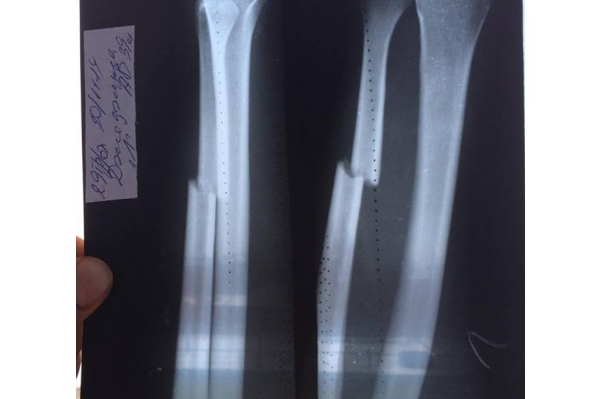

Телеведущий Андрей Джеджула, которого несколько недель назад жестоко избили трое неизвестных, отреагировал на упреки: некоторые заподозрили Андрея в инсценировке инцидента с избиением. На своей странице в соцсети Джеджула выложил устрашающие фото, сделанные в больнице. На них изображен рентген с переломанными костями руки, а также многочисленные швы и ссадины.

На днях Андрей Джеджула провел вечеринку в одном из столичных клубов. Ведущий выглядел весьма жизнерадостным, а следов от побоев или гипса на сломанной руке у артиста не наблюдалось. “Специально для недалеких людей, которые ассоциируют любой вид перелома с гипсом, уточню - при сложных видах переломов, как в нашем случае, со смещением и осколками делается операция. Кость собирается, ставится на место и крепится с помощью титановой пластины. Никакой гипс уже не нужен - он не поможет“, - подчеркнул Колонський.